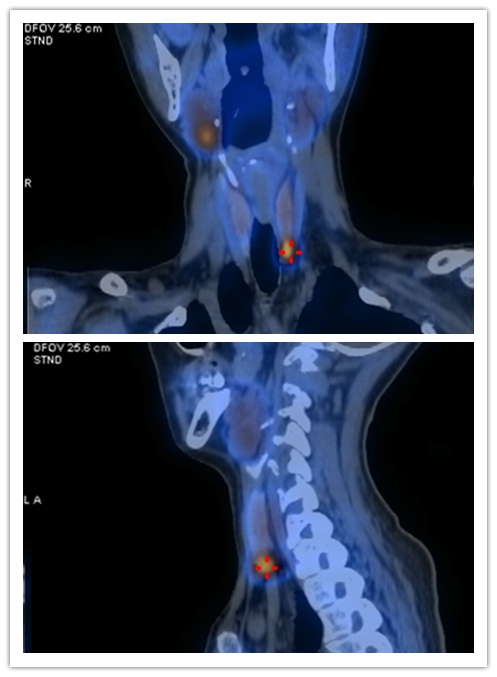

查糖尿病,却查出导致十年肾结石的“罪魁祸首”竟在脖子上

因口干、乏力,41岁的彭女士到捷克论坛 查是否患有糖尿病,没想到却歪打正着,查明反复发作十余年肾结石的原因是甲状旁腺上长了个肿瘤。专家提醒,甲状旁腺出现问题时,可能出现泌尿系结石、乏力、易疲劳、食欲下降、烦躁、记忆力减退等症状。

接诊的内分泌二病区主任赵新兰仔细询问病史、体查后发现,患者不是糖尿病,而有可能是一种较为少见的甲状旁腺亢进症(简称甲旁亢)。经检查,最终确定彭女士反复发作的泌尿系结石、逐渐加重的疲倦感等症状,都是由于体内的甲状旁腺瘤分泌过多的甲状旁腺激素所导致。目前经一系列治疗,5月20日,彭女士血钙恢复正常,症状好转出院。